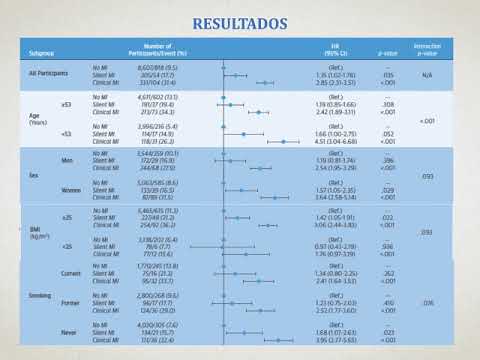

Ablación de la FA en la insuficiencia cardíaca. Estudio CASTLE. Dra. Ana Laura Mori. Residencia de Cardiología. Hospital C. Argerich Buenos Aires